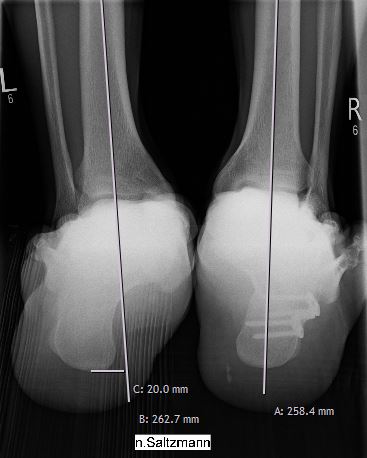

Bei einem Knick-Senkfuß-Spreizfuß kommt es zu einer Abflachung des Längsgewölbes im Sinne eines Platt- oder Senkfußes. Zusätzlich kippt die Ferse / der Rückfuß nach innen (ähnlich eines X-Beines am Knie). Hierdurch entsteht eine einseitige Belastung des Fußes/Sprunggelenkes, welches zu Beschwerden anfangs im Innenbandbereich und im Verlauf auch im Bereich des Außenbandbereiches führen kann.